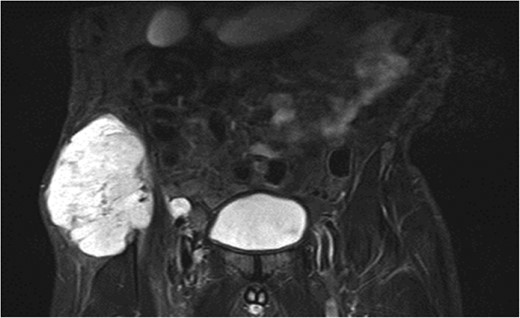

A previously fit and well 68-year-old male presented with a 6-month history of pain in the right hip. On examination this was localised to the superior area of the hip joint where a bony mass could be palpated. A pelvic radiograph was performed (Fig. 1) showing a bony exostosis on the right iliac wing. To characterise the lesion further, a pelvic Magnetic resonance imaging (MRI) scan was performed (Fig. 2). Appearances were consistent with an osteosarcoma and referral to the local sarcoma centre for histological investigation was made. Surprisingly, sampling from biopsy showed invasive well-differentiated adenocarcinoma. Staging computed tomography (CT) scanning did not reveal a primary source for the tumour but did identify thickening of the descending colon (Fig. 3) and lymphadenopathy involving the left supraclavicular, thoracic, paravertebral, retro-crurual and right inguinal regions. There was no evidence of tumour in the liver, lung or other parts of the skeleton. Subsequently, colonoscopy identified the thickened lesion as a hepatic flexure adenocarcinoma (Fig. 4). Biopsy at the time of endoscopy revealed the lesion at the hip to be a metastasis.

CT abdomen demonstrating thickened segment of ascending colon.